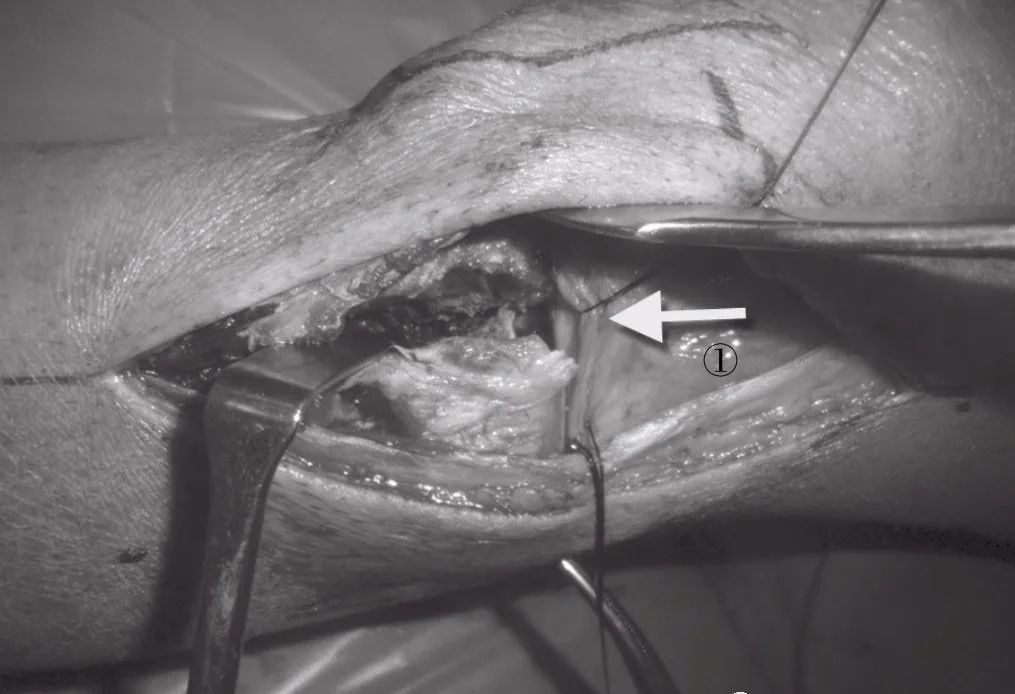

图7 切开筋膜后,蓝色处显示关节囊膨胀(①箭头)。可以看见半月板下的平台(②箭头)

图8 从半月板下切口打开膝关节。将半月板(①箭头)多重缝合。

侧面的:切口起自靠近关节线,由股骨外侧髁至Gerdy结节,然后弧形转向胫骨干。阔筋膜张肌在胫骨结节线切开,分开为前侧和后侧皮瓣。远端延伸的前部深筋膜可用剪刀剪开。远端的前部肌间隔从胫骨近端前外侧侧面地反映。前方的阔筋膜张肌从关节囊一直到髌腱的边界都被抬起。后方被腓骨头(外侧副韧带附着处)限制(图7)。关节囊呈淡蓝色、柔软的袋状,划分胫骨上部和可能的关节线(图7)。皮下注射针用于寻找半月板下的空间。关节囊横向地打开,在半月板下的平面锐性切断冠状纤维,以**化地改善关节内骨折的显示。半月板穿过两到三条线(不可吸收)并向上提起。内翻膝关节将有助于增加关节面的显露(图8)。

图9 利用翻书样技术旋转翻开外侧骨折块进一步显露关节内管折。①箭头:外侧平台骨折块;②箭头:关节内塌陷